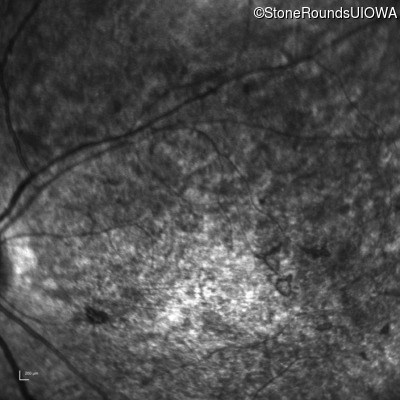

Infrared Fundus Photograph - Right - 20/400 sc

Exemplar